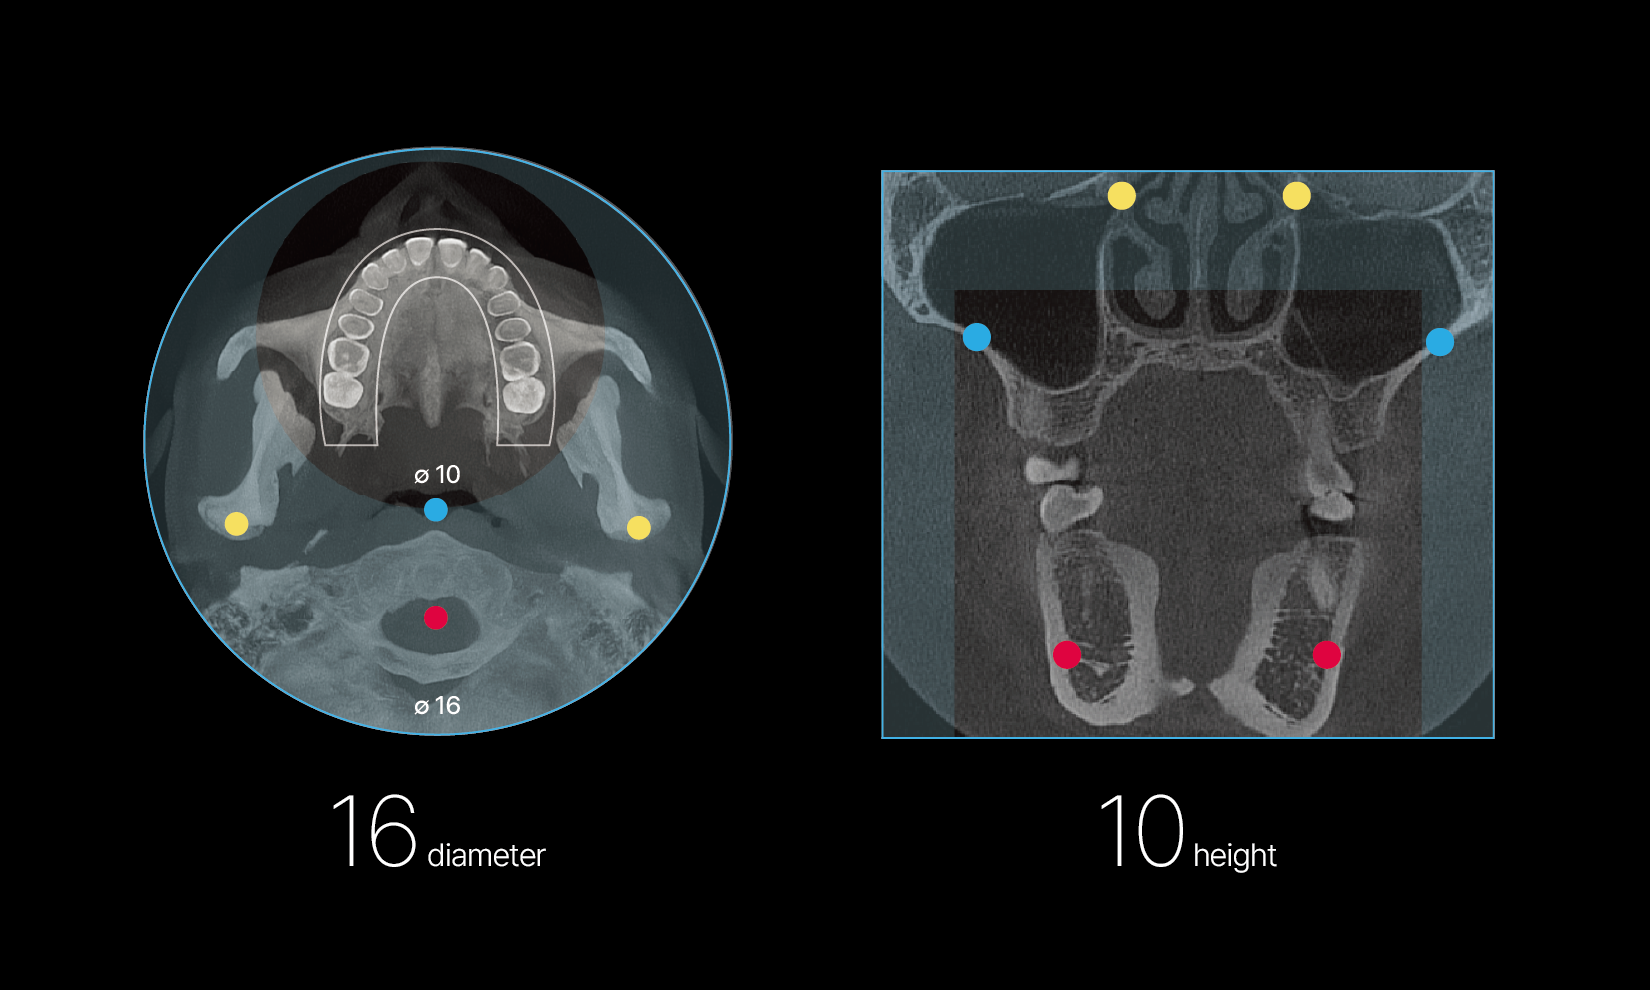

RAYQuantum allows for quick and easy selection of the scan area through predefined FOV options, supporting a wide range of dental procedures, including implant planning, orthodontics, complex impactions, bilateral TMJ, sinus and airway analysis.

Utilization in a wide clinical range with an extended FOV

Essential coverage for confident diagnostics

RAYQuantum’s expanded 16×10 Field of View ensures clear capture of essential anatomical areas across various diagnostic needs.

Predefined FOV options for ease and convenience

Predefined FOV options for ease and convenience allow quick and effortless selection of the scanning area with just one or two clicks.

Utilization in a wide clinical range with an extended FOV

Essential coverage for confident diagnostics

RAYQuantum’s expanded 16×10 Field of View ensures clear capture of essential anatomical areas across various diagnostic needs.

Predefined FOV options for ease and convenience

Predefined FOV options for ease and convenience allow quick and effortless selection of the scanning area with just one or two clicks.